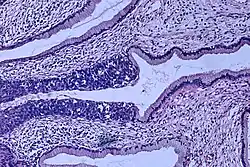

Invasive squamous cell carcinoma of the cervix is characterized by infiltration as irregular anastomosing nests or single cells.[75] This case is poorly differentiated. H&E stain. -

Cervical squamous cell carcinoma generally shows diffuse staining of both nuclei and cytoplasm on p16 immuno-

histochemistry (except verrucous variant).[76] -

Invasive cervical squamous cell carcinoma on H&E histopathology and Ki-67 immunohistochemistry. The latter correlates well with the degree and level of dysplasia.[77] -